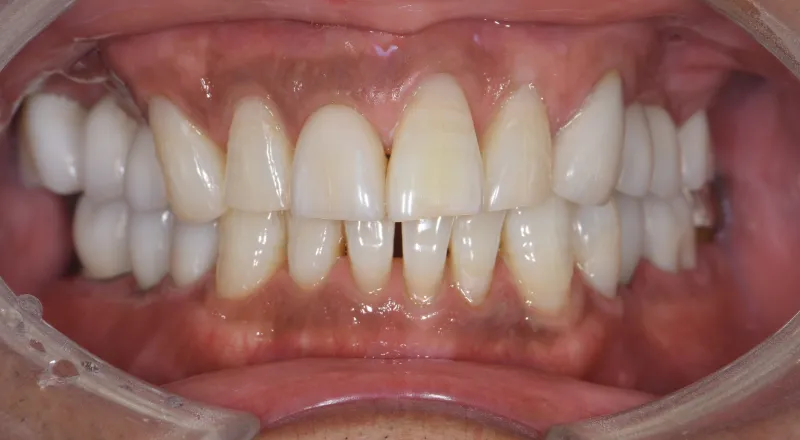

| 主訴 | 歯が抜けている。 入れ歯のところをインプラントしたい |

|---|---|

| 診断名 | 歯の欠損、義歯不適合 |

| 年齢・性別 | 63歳・男性 |

| 治療期間・回数 | 1年3ヶ月・33回 |

| 治療方法 | 精密根管治療、ジルコニアクラウン、GBR、インプラント、ホワイトニング |

| 費用 | 3,949,000円 最高プラン (費用を抑えたプランも提案可能) |

| 治療上のリスク |